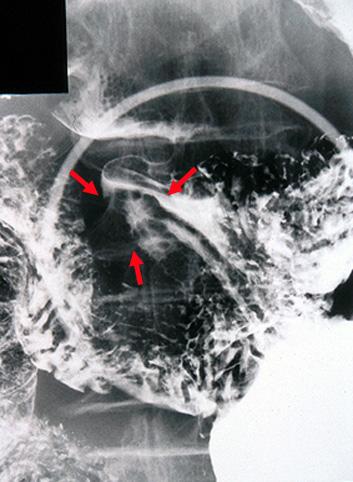

clasificación del pacienteTumor Epitelial Maligno/Adenocarcinoma

parte(separada por órganos)estómago(región)/antro

método de exámenRayos X

clasificación ectoscópica de tumoresTipo 0(tipo superficial)/Tipo IIc(IIc)

diámetro mayor del tumor1 - 9

grado de penetraciónm